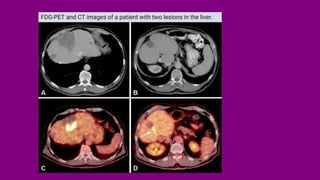

FDG-PET and CT images of a patient with two lesions in the liver.

FDG-PET and CTimages of a patient with two lesions in the liver.